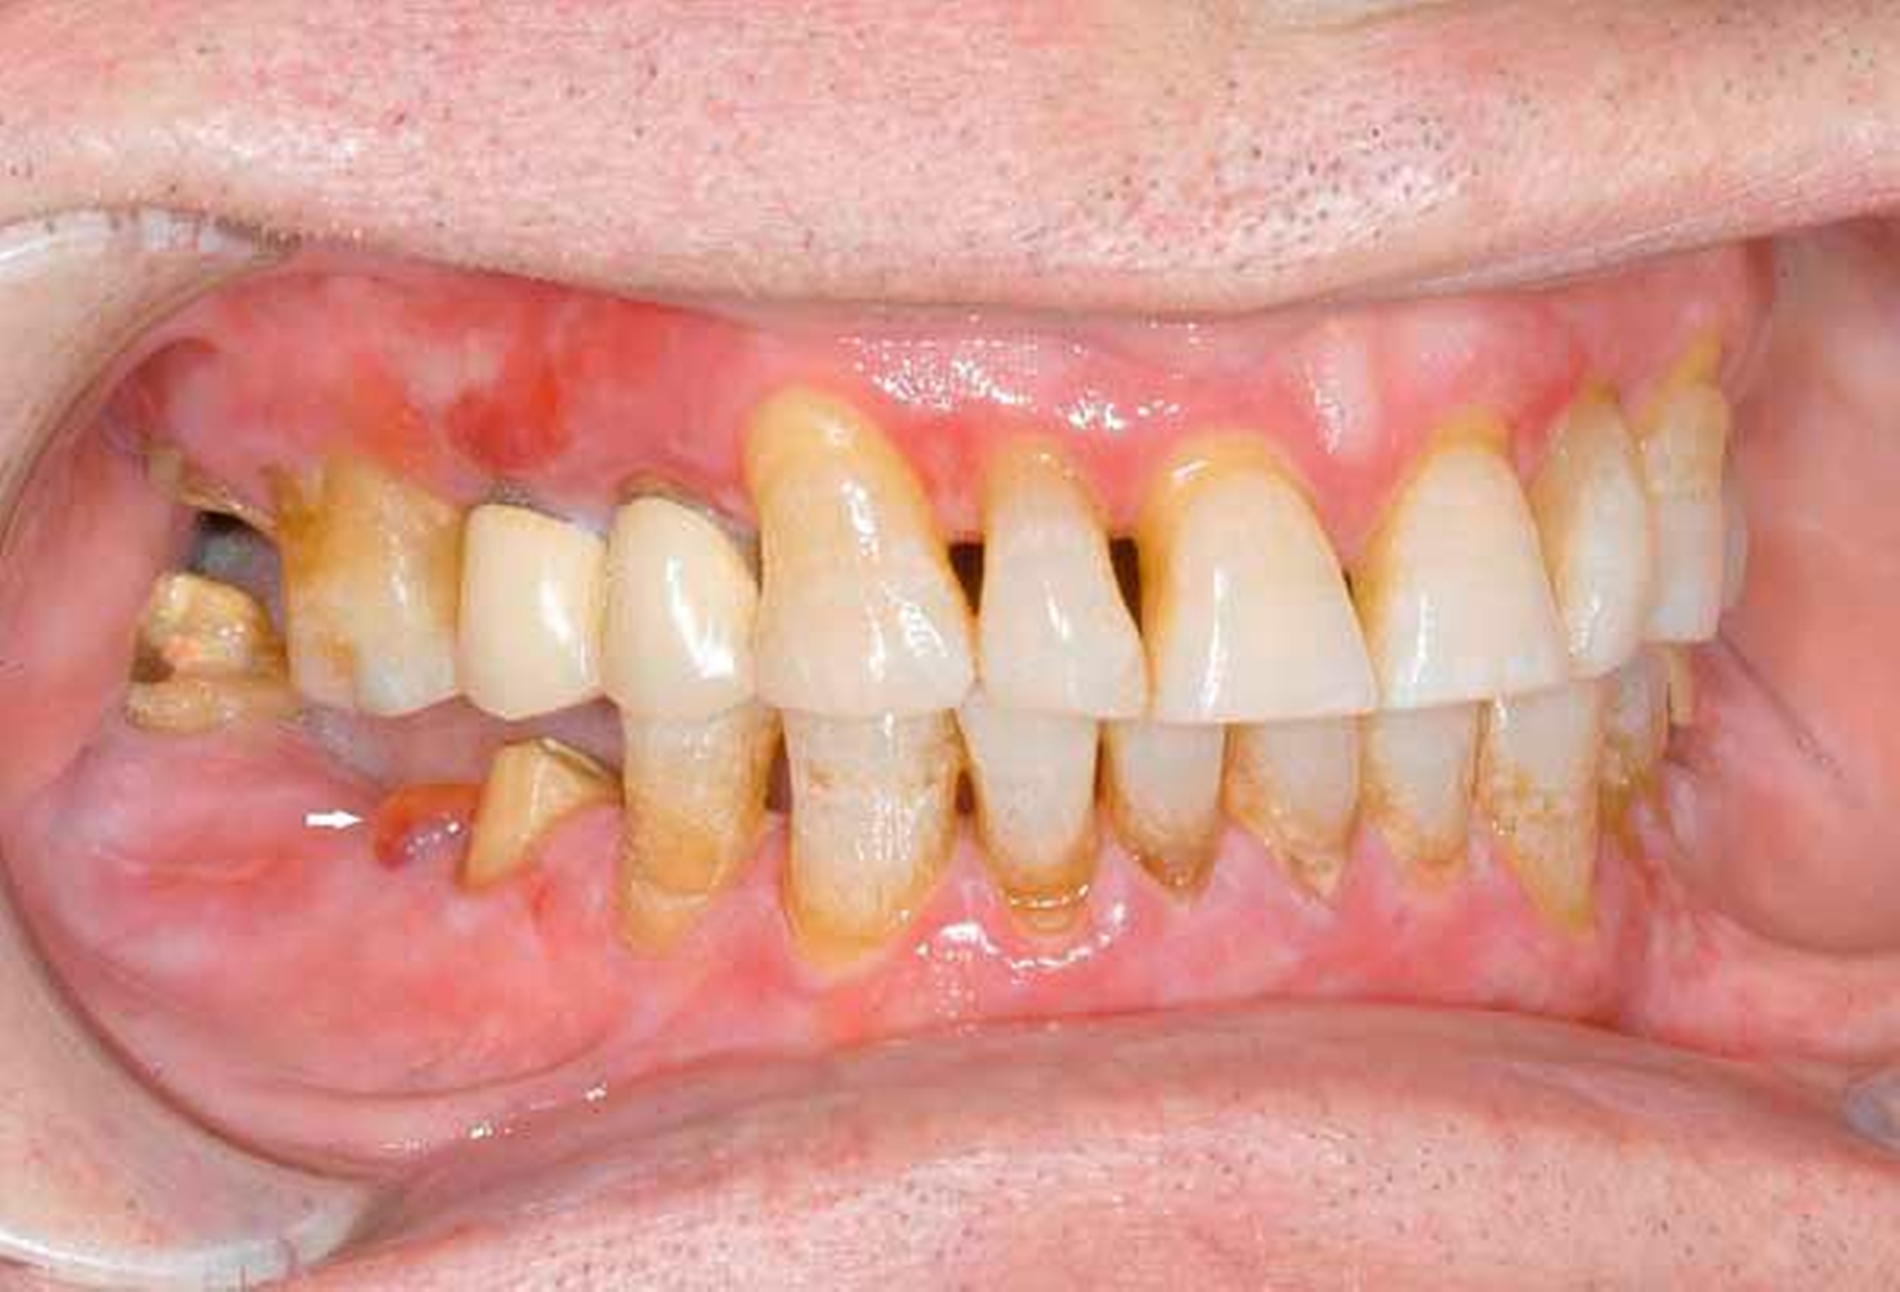

Eine 20-jährige Frau wird mit multiplen Nichtanlagen (Oligodontie) vorstellig. Sie berichtet, dass ihre Milchzähne vollständig angelegt waren. Mit dem einsetzenden Zahnwechsel habe sich jedoch herausgestellt, dass bei ihr multiple bleibende Zähne nicht angelegt waren. Insbesondere in der Pubertät habe sie sehr darunter gelitten, da sie wegen ihrer Zähne von den Mitschülern missachtet worden sei. Von verschiedenen Zahnärzten sei sie zwar auf die Möglichkeit einer Implantatversorgung hingewiesen worden, diese könne sie sich allerdings nicht leisten. Bei der intraoralen Inspektion zeigen sich ein seitlicher offener Biss, Formanomalien der mittleren Oberkiefer-Schneidezähne sowie multiple verbliebene Milchzähne. Der radiologische Befund bestätigt den Verdacht auf eine Oligodontie. Auf Nachfrage berichtet die Patientin, dass sie „wenig schwitze“.

Aufgrund der Befunde wird der Patientin eine genetische Beratung bei Verdacht auf eine WNT10A-Mutation vorgeschlagen. Die genetische Untersuchung bestätigt letztlich den Verdacht einer ektodermalen Dysplasie.

Oligodontie im Zusammenhang mit einer ektodermalen Dysplasie.